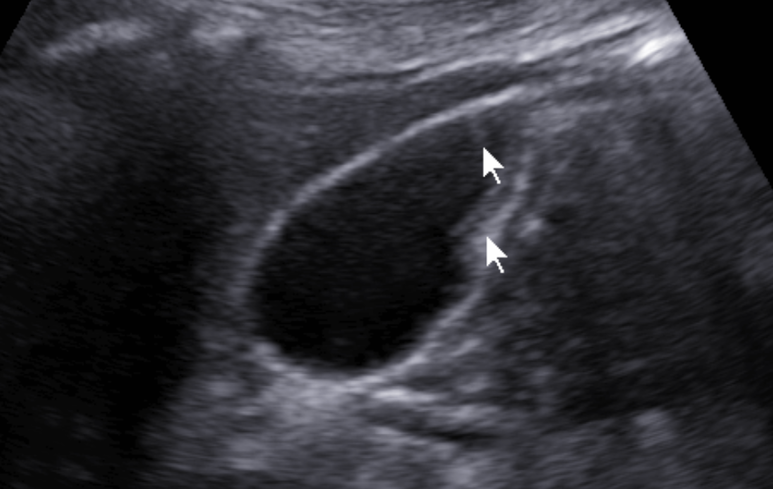

초음파 시행; 후방 음영 소실을 보이는 작은 담석들이 관찰됨

자세 변화에 따라 이동하는 모습